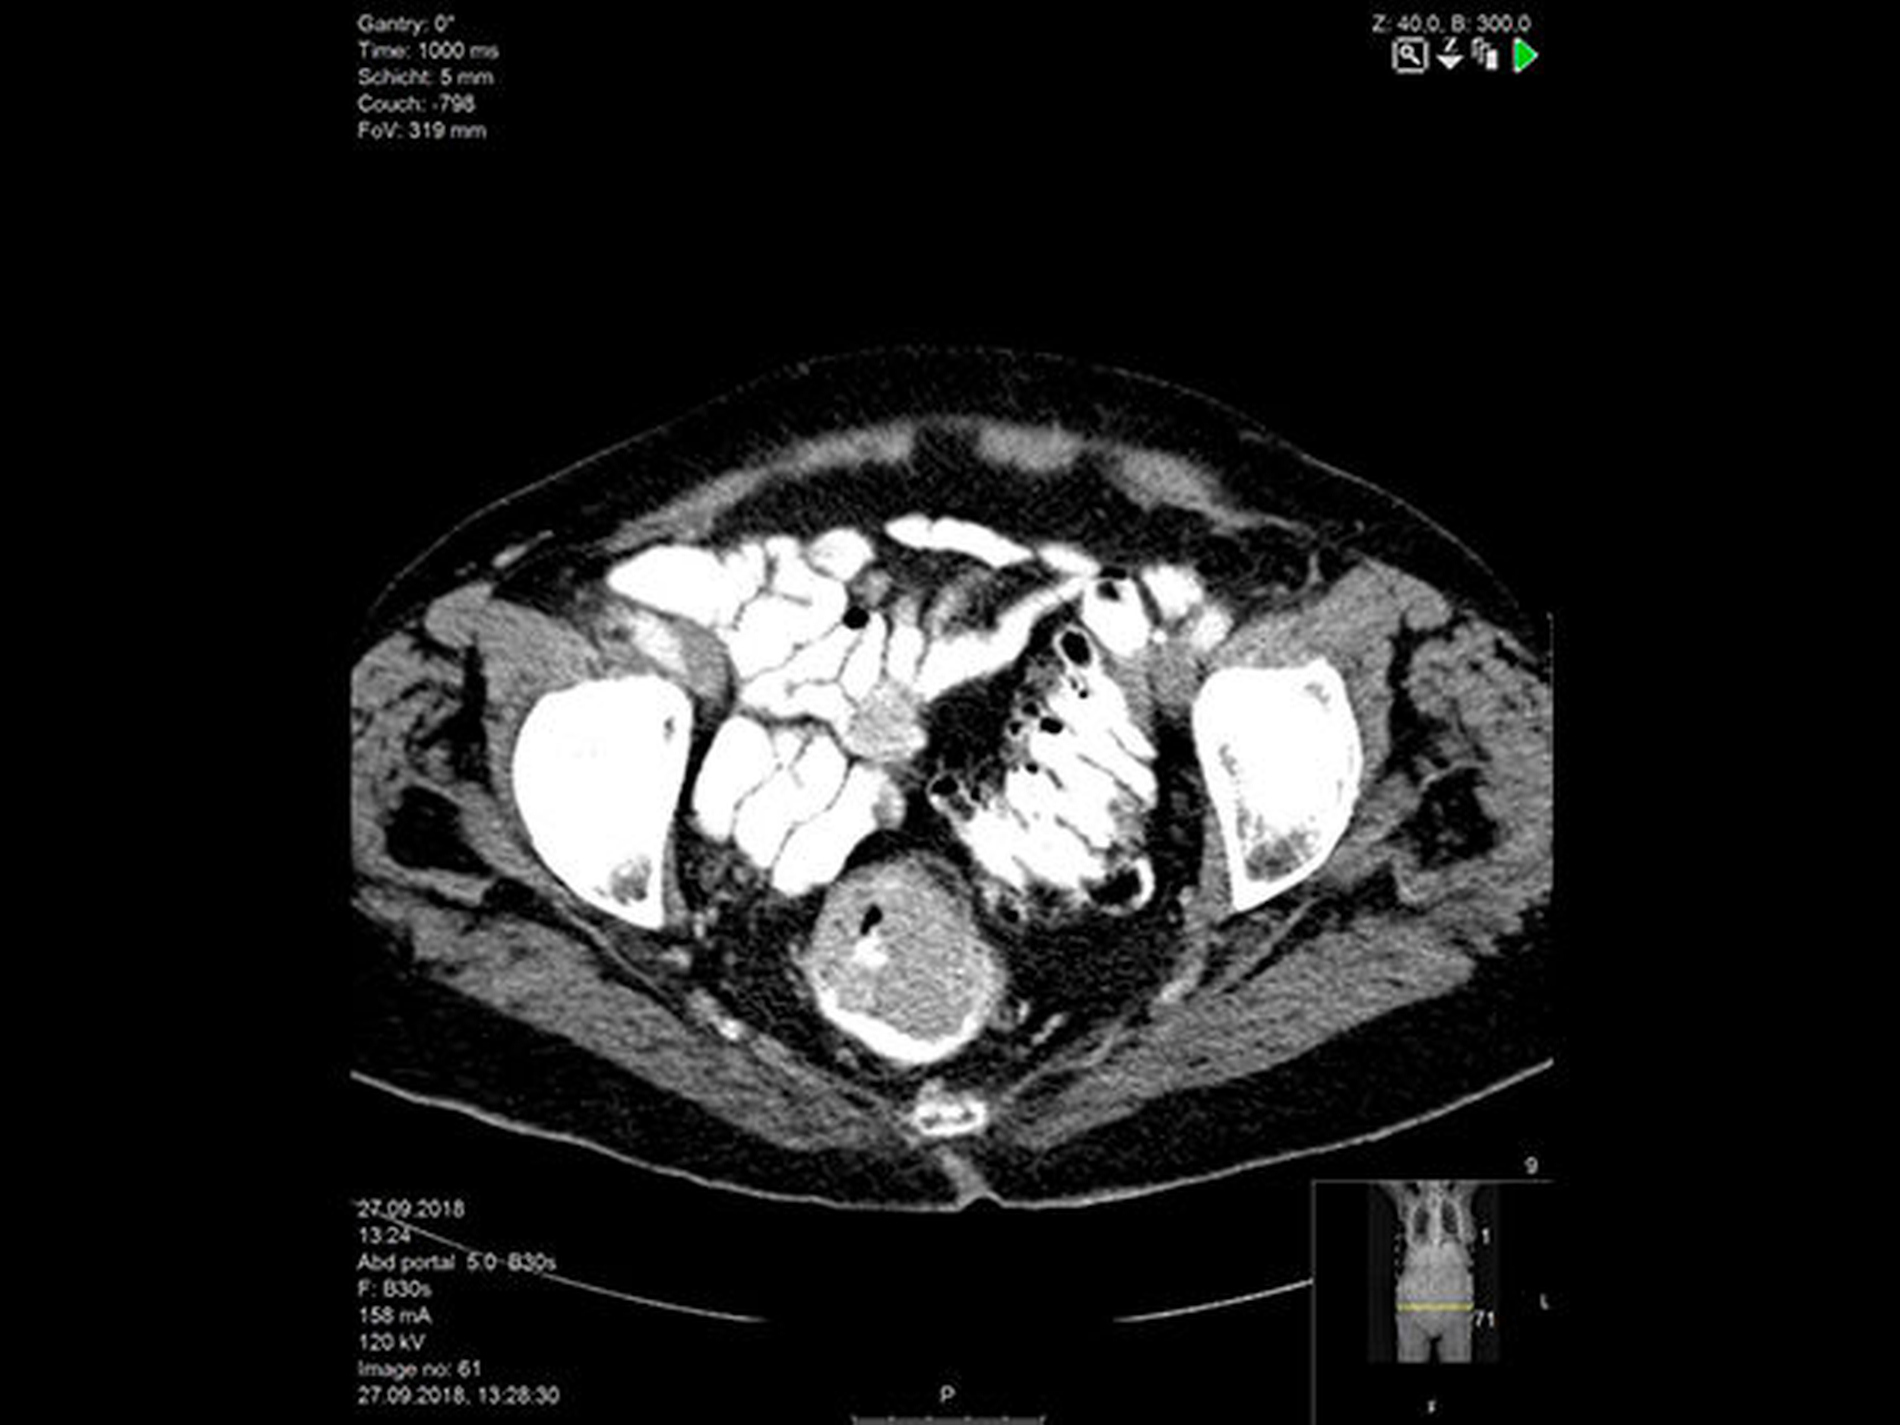

Die CT-Untersuchung von Hals, Thorax, Abdomen und Becken zeigt

ein ausgedehntes Rektumkarzinom mit perifokaler Lymphadenopathie, bipulmonalen und hepatischen Metastasen

(Abbildung 4).